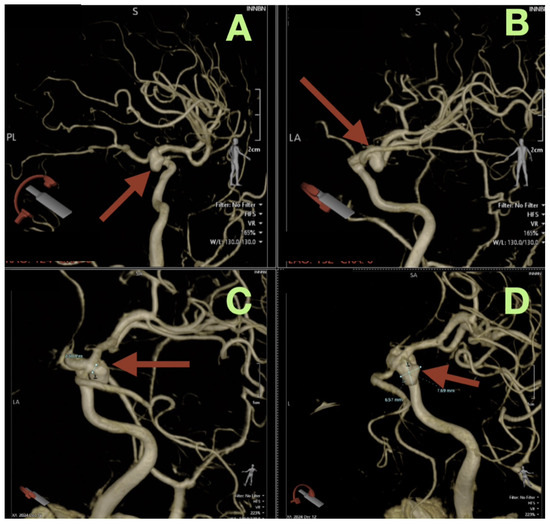

The first image obtained was a non-contrast cranial CT, which showed that there was an SAH (Fisher grade 4), hemorrhage into the ventricles of the brain, and generalized cerebral edema, along with evidence suggesting that the patient had acute hydrocephalus. Due to this verified hemorrhage pattern and significant risk of rebleeding, the patient underwent physiologic stabilization as part of the preoperative process; the patient was intubated and maintained a PaCO2 level between 35 and 38 mmHg to avoid hypercapnic related intracranial hypertension, and the patient’s arterial blood pressure was continuously monitored using nicardipine to keep the systolic blood pressure between 110 and 130 mmHg to decrease the risk of rebleeding while maintaining adequate cerebral perfusion. Selective right internal carotid artery angiography, including DSA, confirmed a saccular aneurysm located at the posterior communicating segment of the right internal carotid artery with a posteriorly oriented dome and a very narrow neck (<3 mm); the aneurysm arose from a branch critical area where a fetal type posterior cerebral artery (fPCA) branched off the aneurysm neck plane (Figure 1A–D). The presence of the aneurysm at a branch critical area made it necessary to reconstruct the junction of the aneurysm neck to the parent vessel, versus simply closing the aneurysm neck to preserve the lumen of the fPCA. Three-dimensional rotational angiography further defined the operative geometry and confirmed the aneurysm’s neck diameter to be approximately 2.5 mm and the maximum sac diameters to be approximately 7.7 × 6.6 mm (Figure 2C,D). The aneurysm was located at the carotid–PCom junction and was closely associated with the oculomotor cisternal corridor providing a potential anatomic basis for the intermittent pupillary variability observed during the acute phase of hemorrhage.

Figure 2.

Three-dimensional rotational angiography reconstructions. (A) Oblique three-dimensional view demonstrates the saccular aneurysm at the right carotid communicating segment (arrow), with posterior dome projection and the aneurysm base seated at the junctional complex. (B) Complementary oblique view highlights the aneurysm’s relationship to the communicating region (arrow), emphasizing the shared plane between the aneurysm base and the posterior circulation outflow tract in the fetal PCA configuration. (C) High-magnification reconstruction provides a quantitative definition of the neck plane, demonstrating a neck width of approximately 2.5 mm (arrow). (D) Quantitative three-dimensional assessment demonstrates maximal aneurysm dimensions of approximately 7.7 × 6.6 mm (arrow) and reinforces the anatomic convergence of the aneurysm neck with the fetal PCA origin, the critical determinant of junction-preserving exclusion.